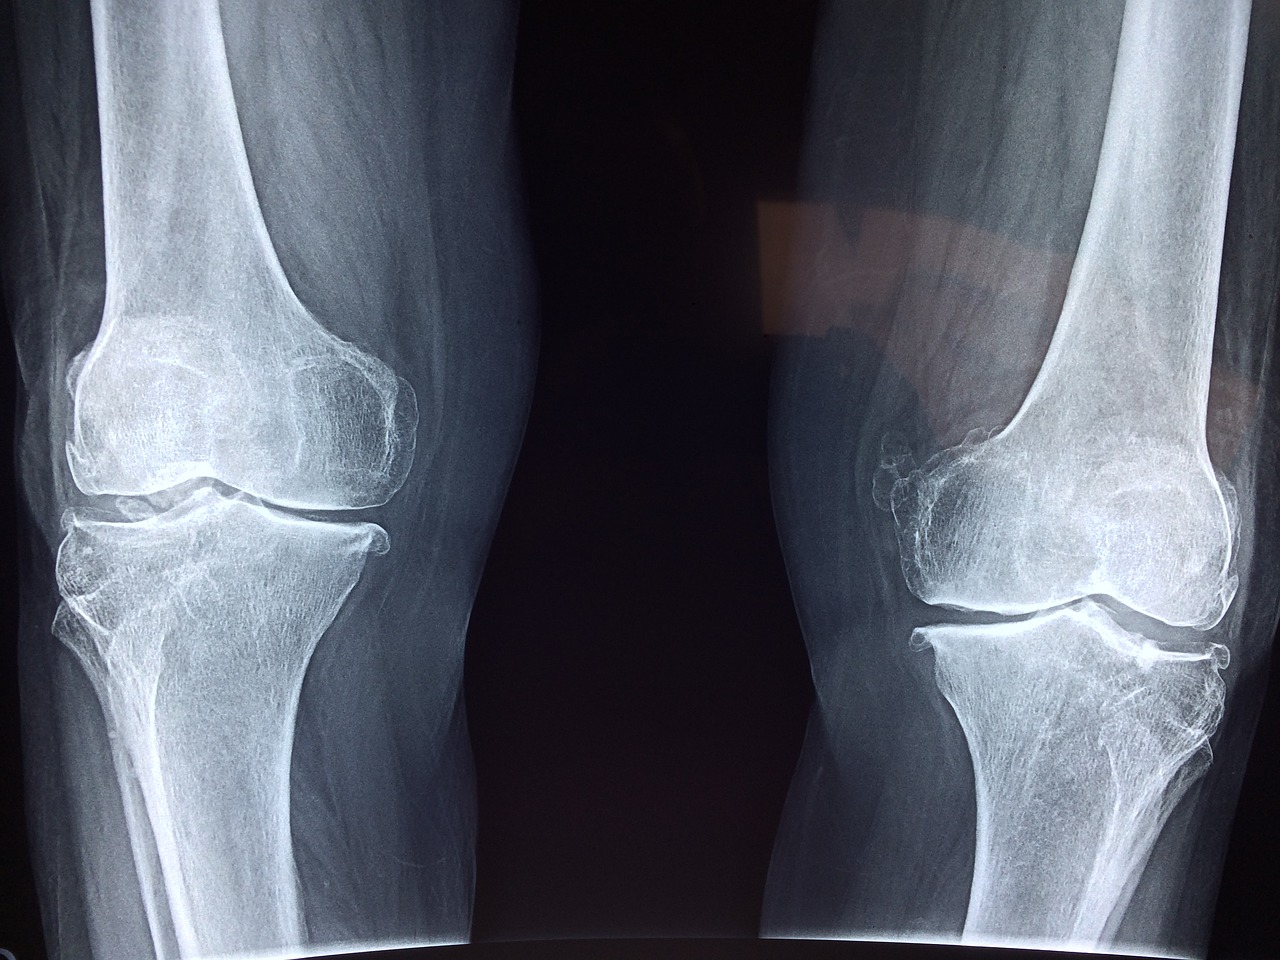

뼈가 다쳤을 때

뼈가 다치는 경우도 있습니다. 사실, 골절이 걱정된다고 오는 많은 경우 중에 골절이 아닌 경우가 더 많습니다. 그렇다 하더라도 어디에 부딪히거나 몸이 과도하게 꺾여 뼈에 충격이 갈 경우 그 부위에 ‘어혈’이 생기게 되기때문에 침치료 등을 할 때 이런 점을 함께 고려하여 치료합니다. 또한, 만약 정말로 ‘골절’이 생긴 경우에는 크게 세 가지로 나눌 수 있는데요, 1) ‘선상골절’이라고 해서 뼈에 실금은 갔지만 어긋나지는 않은 경우, 2) 뼈가 약간 어긋났으나 수술을 필요로 하지 않는 경우, 그리고 3) 수술을 필요로 하는 골절입니다. 1, 2번 같은 경우에는 한의원 치료를 위주로 하고, 3번 같은 경우에는 수술 전후로 한의원 치료를 병행하게 됩니다. 침, 뜸, 부항, 약침시술을 받고, 한약(탕전한약, 또는 보험한약)을 함께 복용하면, 뼈의 유합속도가 더욱 빨라지고, 후유증을 예방해주게 됩니다. 후유증은 한 번 생기면 돌리기가 힘듭니다. 그래서 후유증이 생기기 전, 뼈가 완전히 붙기 전에 미리미리 이런 치료들을 받는 것이 중요합니다.